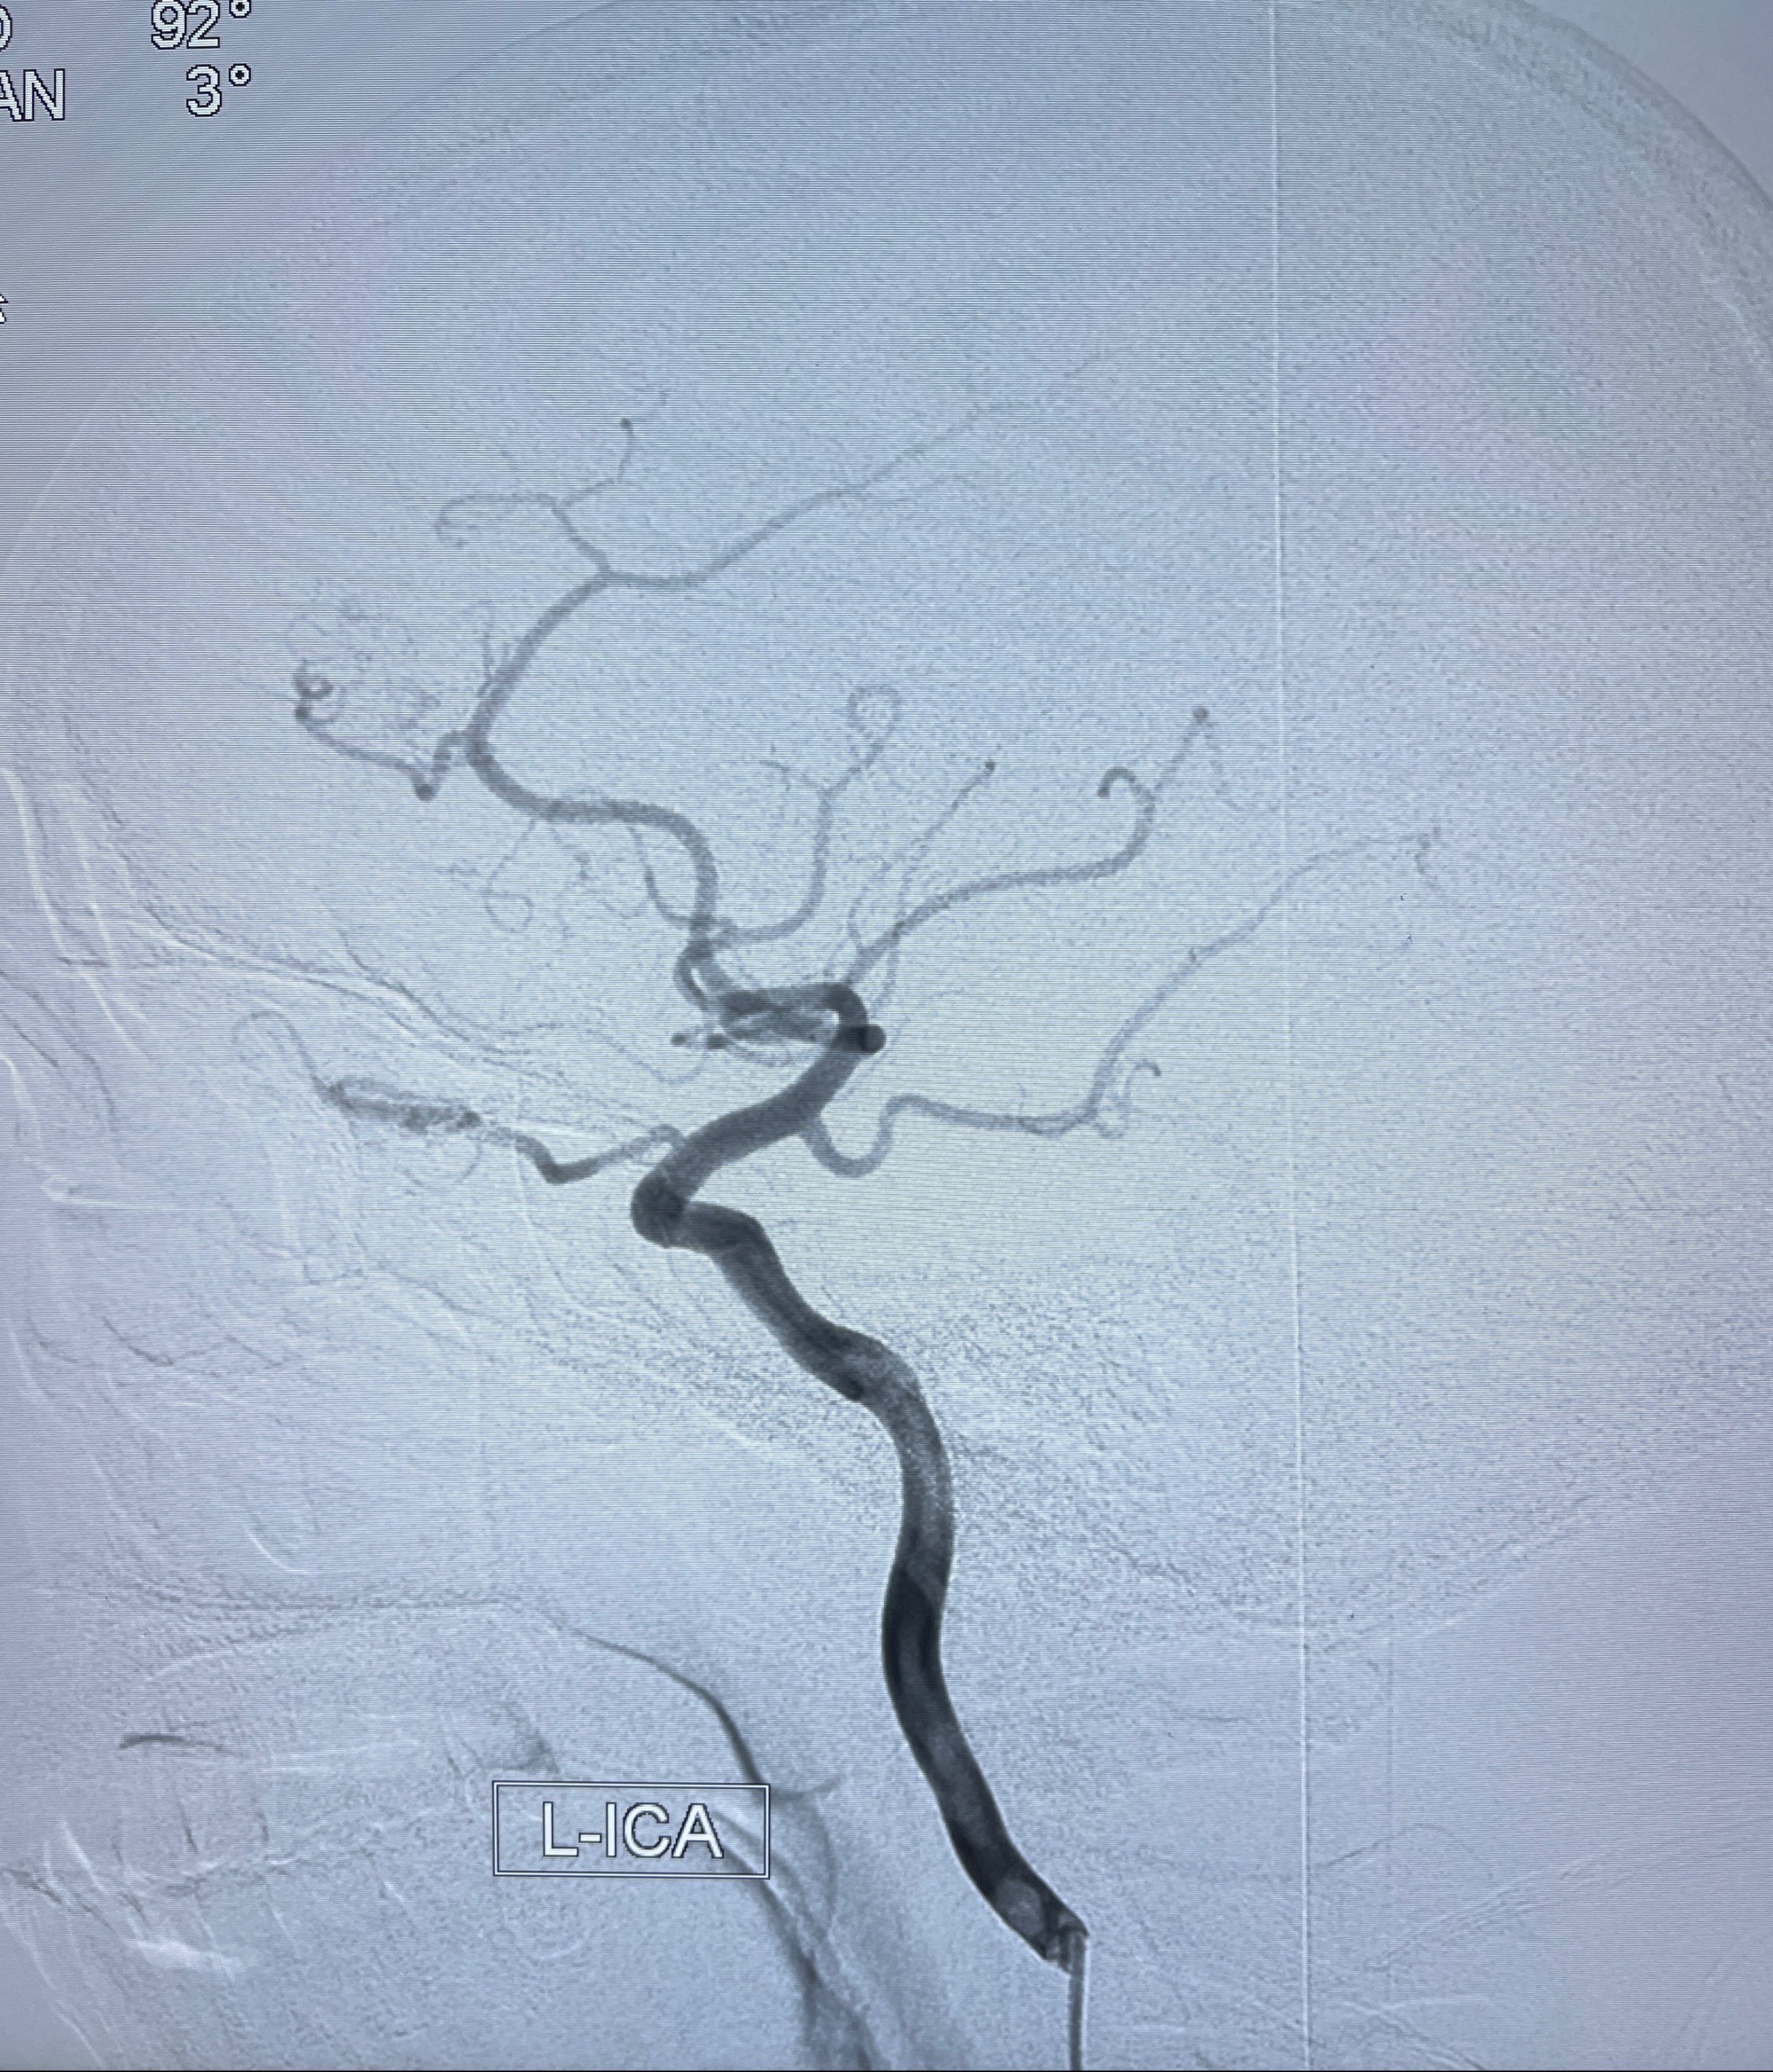

2023年8月21日]景德镇市第一人民医院脑血管造影检查,提示:主动脉弓、双侧颈总动脉、锁骨下动脉造影未见异常,左侧大脑前动脉静脉瘘。

2023-09-13全脑血管造影:前颅底硬脑膜动静脉瘘,供血动脉为双侧胼周动脉、眼动脉脑膜支,静脉向上矢状窦方向引流